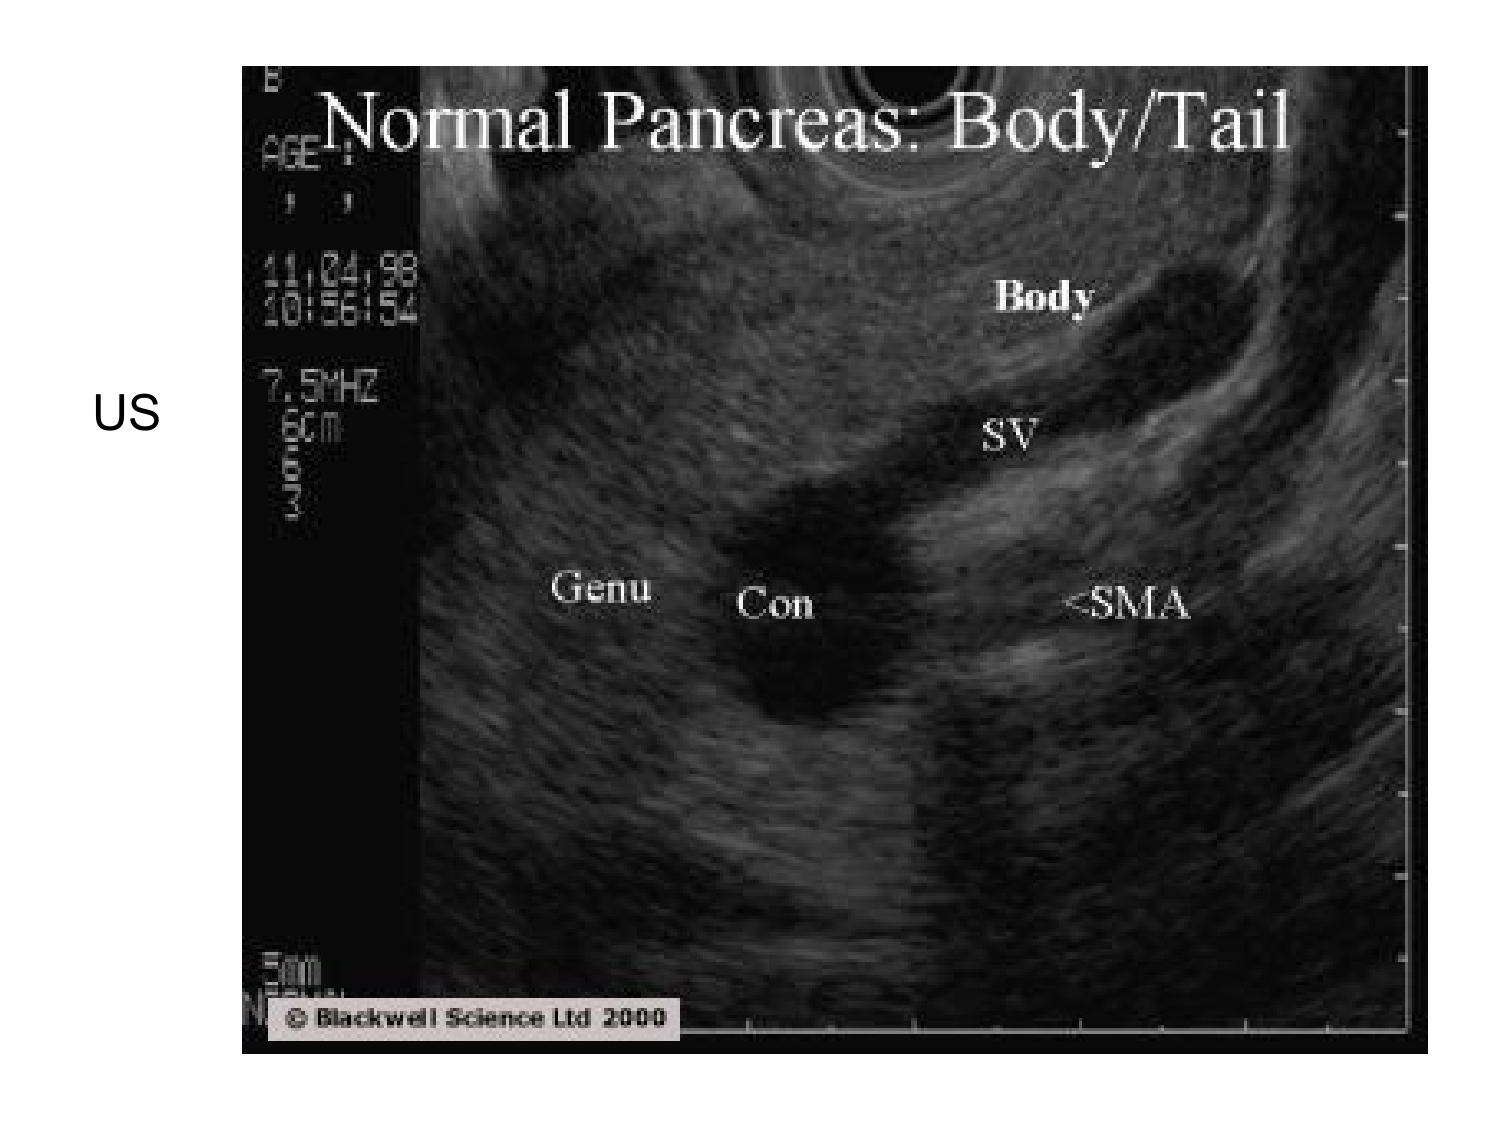

Anatomie du système endocrinien2

Bases de l'anatomie · 92 pages · 12 sections